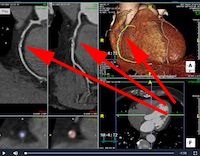

Our workstation images are shown in example videos below – in this case they reveal critical narrowing in two of three coronary vessels.

In these images the intravenous contrast is shown in grey/white filling the coronary vessels that track over the surface of the heart.

Dense coronary calcification is seen as bright white (same density as the breast bone and ribs also seen).

A coronary narrowing or stenosis caused by cholesterol deposits and atheroma build up can be seen as a filling defect (follow red arrows). A stenosis is generally only ‘flow-limiting’ (and worth stenting) if more than 75% of the cross section of the artery is obstructed by the coronary atheroma, as shown in the Right Coronary artery and left circumflex arteries below, but not in the left anterior descending vessel in this case.

Red arrows indicate the stenosis or narrowed section of the coronary artery caused by atheroma or cholesterol deposits.